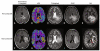

Fluid attenuated inversion recovery (FLAIR) MRI sequences have become an indispensible tool for defining the malignant boundary in patients with brain tumors by nulling the signal contribution from cerebrospinal fluid allowing both regions of edema and regions of non-enhancing, infiltrating tumor to become hyperintense on resulting images. In the current study we examined the utility of a three-dimensional double inversion recovery (DIR) sequence that additionally nulls the MR signal associated with white matter, implemented either pre-contrast or post-contrast, in order to determine whether this sequence allows for better differentiation between tumor and normal brain tissue. T1- and T2-weighted, FLAIR, dynamic susceptibility contrast (DSC)-MRI estimates of cerebral blood volume (rCBV), contrast-enhanced T1-weighted images (T1+C), and DIR data (pre- or post-contrast) were acquired in 22 patients with glioblastoma. Contrast-to-noise (CNR) and tumor volumes were compared between DIR and FLAIR sequences. Line profiles across regions of tumor were generated to evaluate similarities between image contrasts. Additionally, voxel-wise associations between DIR and other sequences were examined. Results suggested post-contrast DIR images were hyperintense (bright) in regions spatially similar those having FLAIR hyperintensity and hypointense (dark) in regions with contrast-enhancement or elevated rCBV due to the high sensitivity of 3D turbo spin echo sequences to susceptibility differences between different tissues. DIR tumor volumes were statistically smaller than tumor volumes as defined by FLAIR (Paired t test, P = 0.0084), averaging a difference of approximately 14 mL or 24 %. DIR images had approximately 1.5× higher lesion CNR compared with FLAIR images (Paired t test, P = 0.0048). Line profiles across tumor regions and scatter plots of voxel-wise coherence between different contrasts confirmed a positive correlation between DIR and FLAIR signal intensity and a negative correlation between DIR and both post-contrast T1-weighted image signal intensity and rCBV. Additional discrepancies between FLAIR and DIR abnormal regions were also observed, together suggesting DIR may provide additional information beyond that of FLAIR.